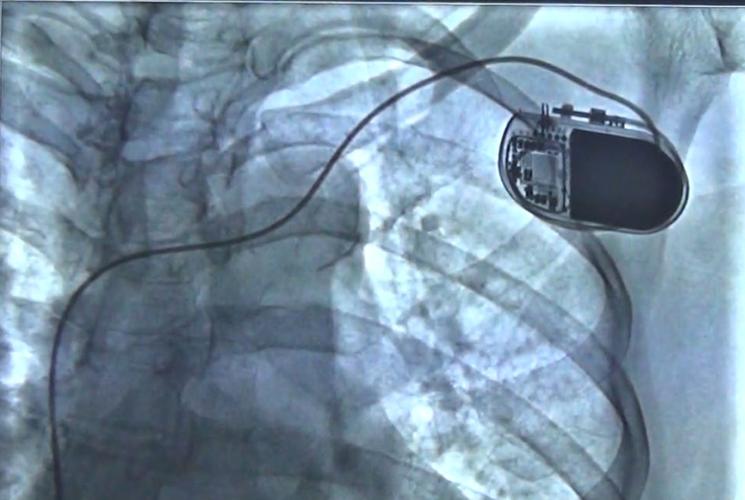

心脏起搏器伤口图片,心脏起搏器手术过程

新蔡同安医院首例永久性人工心脏起搏器植入术成功开展!

厉害了!中医院心内科成功开展首例永久性心脏起搏器植入手术

起搏器被放入心脏过程详解!

仅重2克!桂医二附院成功完成首例无导线起搏器植入手术!

心脏起搏器手术过程

心脏起搏器手术图片

心脏起搏器图片

安装心脏起搏器图片